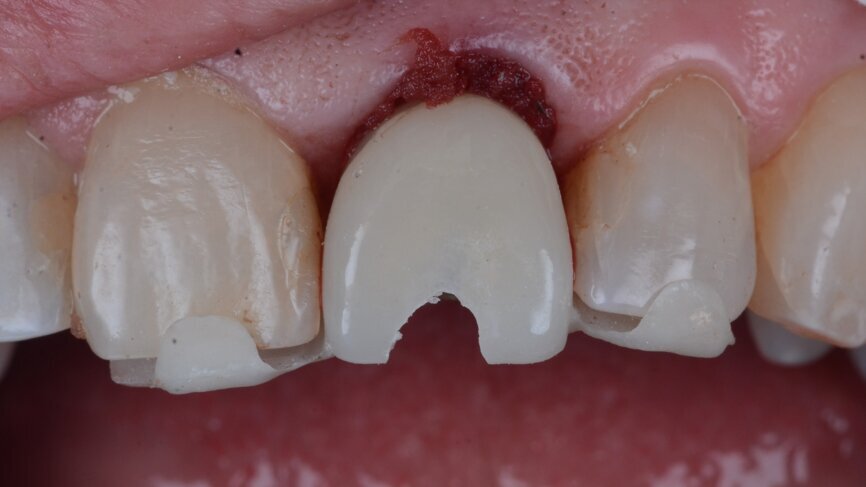

A 53-year-old female patient presented to the office with a fractured left central incisor which had been repeatedly bonded to a ceramic crown (Figs. 1 & 2). Anamneses and examination established good systemic and oral health, a well-balanced occlusion and no smoking habits. Cone beam computed tomography (CBCT) and a periapical radiograph showed external root resorption with very limited insertion into the alveolar bone, insufficient for adequate conventional intra-radicular post placement (Figs. 3 & 4). Considering that the fractured tooth was in the aesthetic zone, the patient requested restoration in the safest and fastest way possible.

A Ø 4 mm temporary abutment with a gingival height of 2.5 mm was placed on to the implant, and it showed no crestal bone interference, allowing for appropriate creation of the emergence profile (Fig. 19). The tooth shell, which was designed and milled in PMMA prior to the procedure (Figs. 20 & 21), was tested to ensure that the contours and retention wings were appropriate and caused no interference (Figs. 22 & 23). The palatal side, including a small portion of the incisal edge, was opened in order to allow screw channel access (Figs. 24 & 25). The lateral wings of the tooth shell allow the provisional temporary crown to stay immobile during the pick-up procedure, which is a common problem clinicians face when performing the immediate pick-up technique. The tooth shell was bonded to the temporary abutment using flowable light-polymerising composite, and a slim emergence profile was created to the subgingival portion using the same material (Fig. 26). At this point, the retention wings were removed. With no compression to the soft tissue, the provisional crown was seated and the incisal edge adjusted to ensure that the antagonist tooth was not touching it in excursive movements. The provisional crown was torqued to 25 Ncm, and the screw access hole properly closed and polished (Fig. 27). The patient was seen seven days later for postoperative and periapical radiographic control (Figs. 28 & 29).

Prosthetic procedure